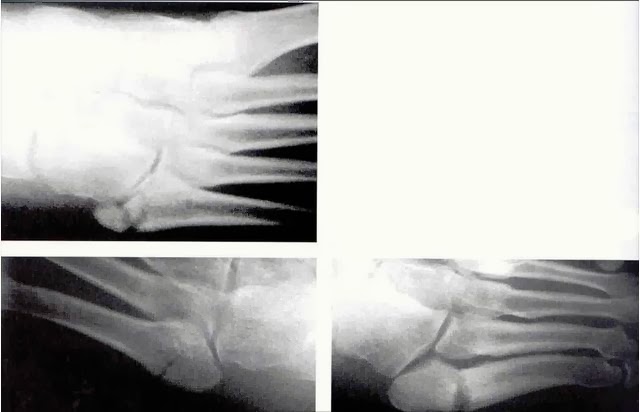

It is one of the most common foot injuries and can be caused by either a sudden injury or repeated stress over. The doctor can use a cast or other method to hold the injured foot in place while the fracture recovers. 5th metatarsal base fractures are common traumatic fractures among athletic populations that are notorious for nonunion due to tenuous blood supply. Fifth metatarsal fractures occur on an outer bone of the foot. Its name originates from its association with dancers who often sustain this injury when excessively twisting or rotating the. Anatomic and imaging evidence of a pathogenesis of avulsion of the plantar aponeurosis and the short peroneal. 5th metatarsal fractures have been quite common among elite soccer players in the english premier league over the past five years. If the bones are very close together and you're young and healthy and you protect the fracture site with the boot or a cast you could heal quite rapidly. We must distinguish between the acute traumatic fracture (let us call this a jones type. The majority of the time, these 5th metatarsal fracture not healing? Thais is sometimes called a jones fracture . For the first two weeks following your surgery. It is one of the most common foot injuries and can be caused by either a sudden injury or repeated stress over. This takes approximately 6 weeks of total immobilisation but time varies depending on severity. A jones fracture is a fracture of the 5th metatarsal of the foot. A common type of break in the part of your 5th metatarsal bone closest to the ankle is called a jones fracture. Related online courses on physioplus.